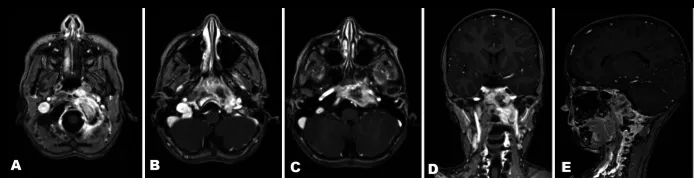

术前MRI,左侧岩骨及斜坡存在强化病灶,注意观察相邻肌肉的受侵情况